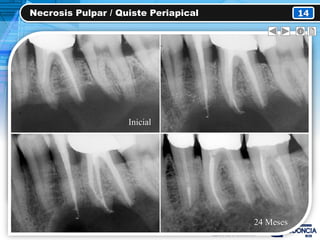

Necrosis Pulpar / Quiste Periapical 14

CLÍNICAMENTE RADIOGRÁFICAMENTE

• Caries grado 3

• Pigmentación coronal

(Gris-Café)

• Zona radiolucida

circunscrita bien definida

(Apical)

• Ensanchamiento del ELP

PRUEBAS DE SENSIBILIDAD ANAMNESIS

• (-) Pruebas térmicas

• (+) Percusión Vertical

• (-) Percusión H.

• (-) Palpación

• Asintomático

• Años de evolución

TRATAMIENTOS

• Tratamiento endodóntico

• Extracción dental

Inicial

24 Meses

TX 4 Años

2 Años